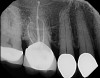

Accurate diagnosis is sometimes the most difficult aspect of daily clinical practice. CBCT has improved the trained practitioner's ability to find hidden periapical pathology, particularly in areas where structures such as the maxillary sinus and zygomatic arch, as well as thick cortical bone, can conceal periradicular lesions (Figure 7 and Figure 8).5-7

Fig 7. 2D radiograph of tooth No. 3.

Figure 7

Fig 8. 3D CBCT image of tooth No. 3 revealing hidden periapical pathology.

Figure 8